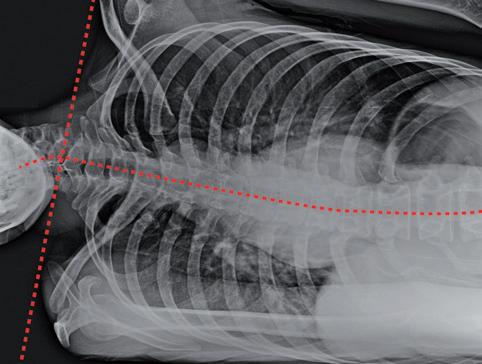

Illustration 2: conséquences d’une épaule surélevée –problèmes de la partie inférieure de la colonne cervicale durant le sommeil

Biomécanique d’un surmenage cervical

Il est essentiel d’analyser les forces qui agissent sur la région cervicale pour concevoir une approche thérapeutique ciblée. Les pathologies affectant les vertèbres cervicales et lombaires sont des afflictions spécifiquement humaines. Ces parties du corps sont particulièrement vulnérables. Nous pouvons effectuer une rotation complète de nos bras. Notre thorax, à la fois plat et étendu, positionne idéalement nos épaules. Plus significatif encore, nous avons de longues clavicules qui font office de contreforts et qui confèrent une mobilité exceptionnelle à nos membres supérieurs. Mais cette machinerie anatomique n’est toutefois pas sans défaut: nous ne pouvons pas dormir sur le ventre ou sur le côté sans solliciter les cervicales.

L’illustration 2 montre à quel point il est difficile de soutenir les points clés de la colonne cervicale inférieure lors d’une surélévation des épaules. Lorsque nous dormons sur le côté, la forme de notre corps s’ajuste à la surface plane du lit, ce qui entraîne une élévation de l’épaule jusqu’au niveau du menton, voire au-delà. Instinctivement, nous positionnons notre oreiller sous notre nuque, mais l’épaule bloque tout soutien à partir de la partie supérieure du cou.